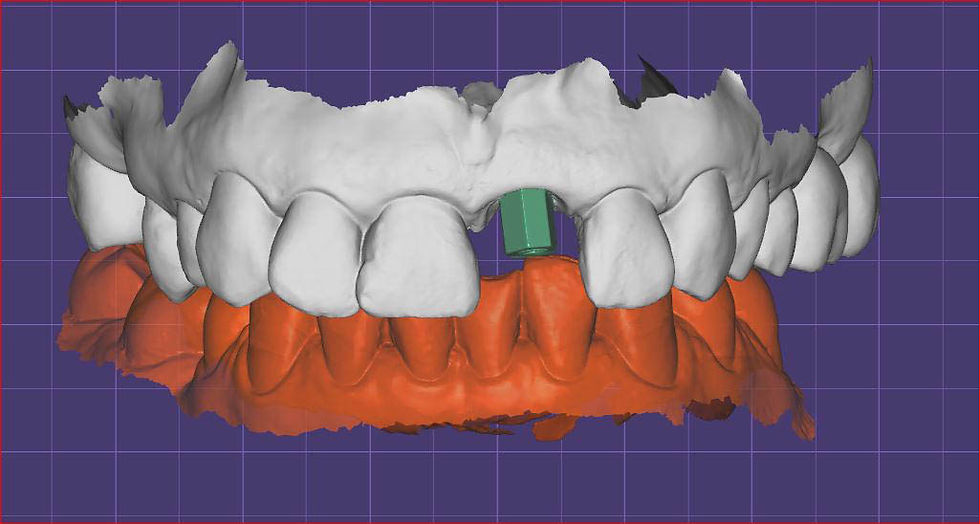

The crown design on the Interfase Dynamica support, which allows the realization of a screw retained crown with palatal displacement of the screw hole, in favor of the final aesthetics.

Final phases of the planning of the definitive crown.